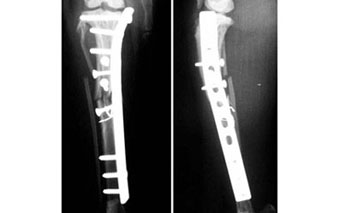

体重1.2kgの猫の脛骨(下腿骨)骨折。

これもピンニングと創外固定をタイインという方法で組み合わせることで、骨折部にメスを入れることなく整復固定しました。

写真上段: 手術前

写真2段目: 手術直後

写真3段目: 手術直後の様子

レーザーでピン刺入部に小さな穴を開けただけで骨折部を開創せず、手術負担が少なかったため、手術直後には着地歩行していました。